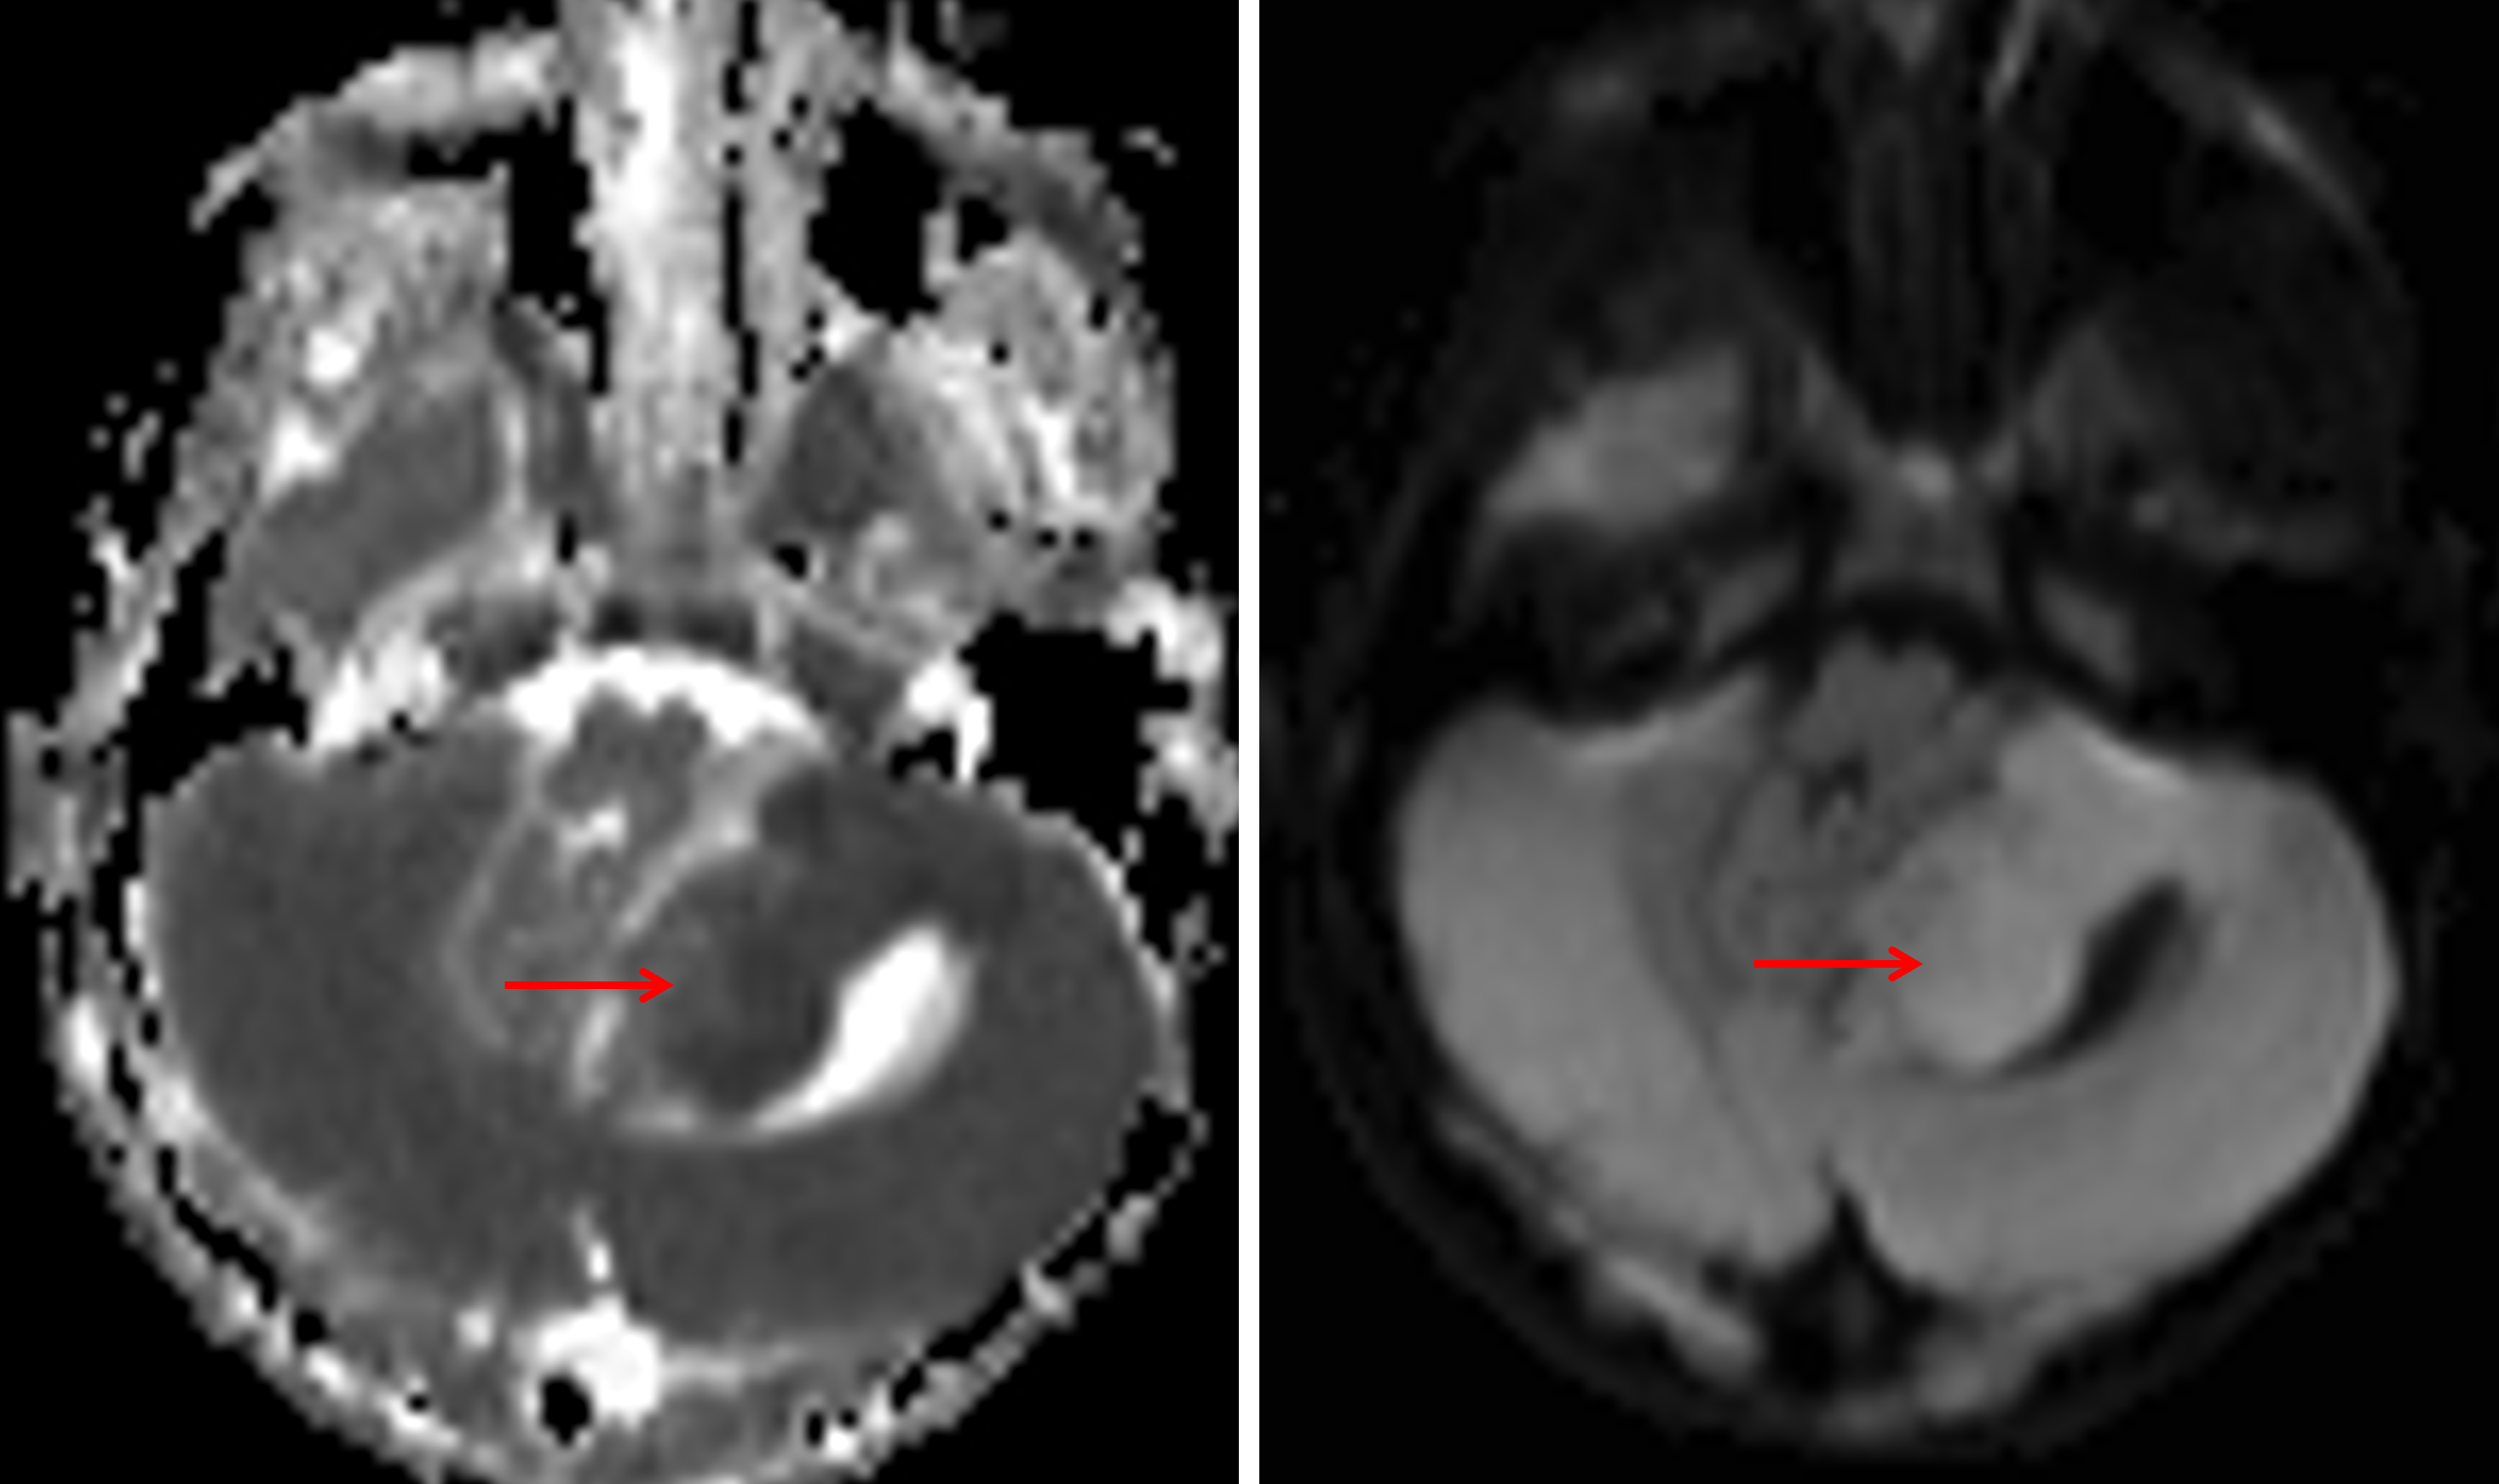

Age: 3

Sex: Female

Indication: Gait instability, confusion

MRI

Medulloblastoma (SHH-activated, TP53 wild-type, nodular desmoplastic histology)